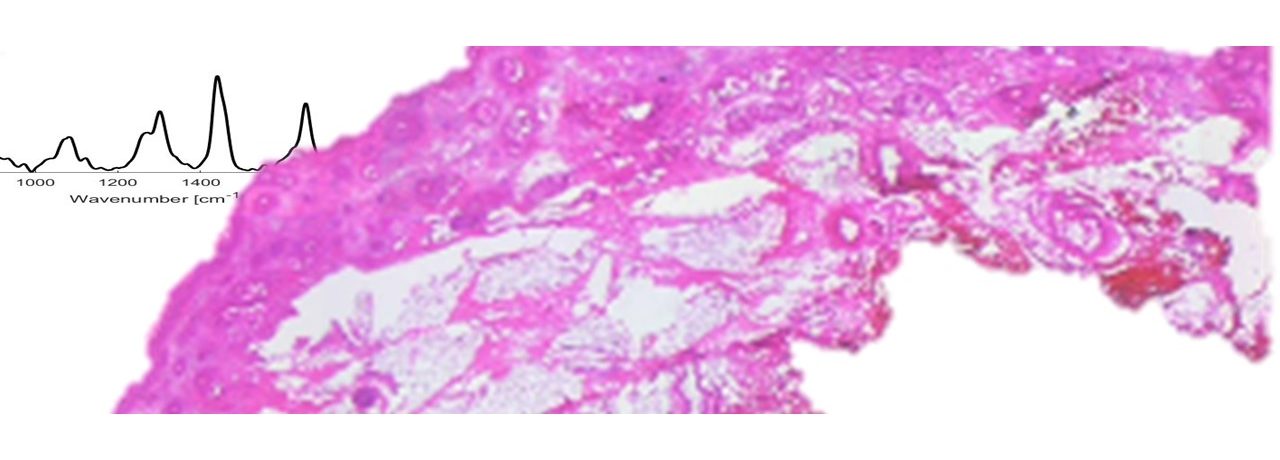

• Image-guided surgery using Raman microscopy

Surgery remains a primary tool to remove cancerous tumors; however, a major challenge of the procedure is incomplete surgical removal leading to recurrence, costly Read more

Image-guided surgery using Raman microscopy